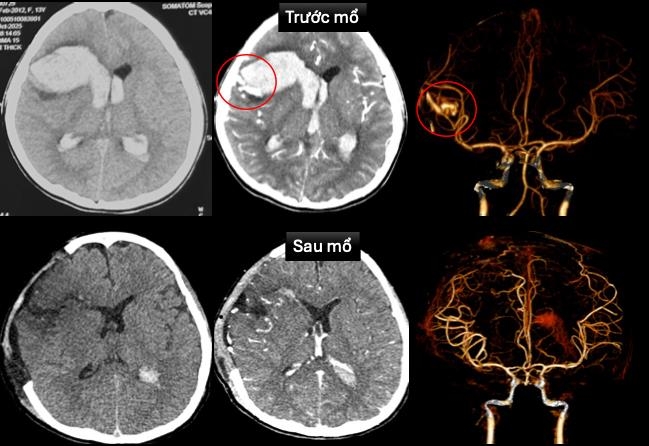

Tại Bệnh viện Nhi Đồng 1, bệnh nhi được tiến hành siêu âm tim và chụp cắt lớp vi tính dựng hình mạch máu não cấp cứu. Kết quả cho thấy bé bị dị dạng động tĩnh mạch vùng trán phải vỡ, gây xuất huyết não lan vào hệ thống não thất, đồng thời ghi nhận bệnh cơ tim xốp - một dạng bệnh cơ tim hiếm gặp.

Hình ảnh chụp cắt lớp vi tính sọ não và dựng hình mạch máu não trước và sau mổ

Bệnh viện đã lập hội chẩn đa chuyên khoa gồm cấp cứu, tim mạch can thiệp, ngoại thần kinh và hồi sức ngoại. Bác sĩ tim mạch đặt máy tạo nhịp tạm thời để ổn định nhịp tim. Tiếp đó, ê-kíp ngoại thần kinh thực hiện mở sọ giải áp, vi phẫu cắt bỏ dị dạng mạch máu não và lấy máu tụ trong nhu mô não và não thất.

Sau phẫu thuật, bệnh nhi được hồi sức tích cực, thở máy, dùng thuốc vận mạch và thuốc chống phù não. Tình trạng cải thiện dần, hiện bé đã tỉnh táo, còn yếu nhẹ chân phải. Tim mạch ổn định, máy tạo nhịp đã được rút và ngưng thuốc vận mạch. Hình ảnh CT sau mổ không còn ghi nhận dị dạng mạch máu. Siêu âm tim cho thấy chức năng co bóp cơ tim cải thiện (EF 65%).